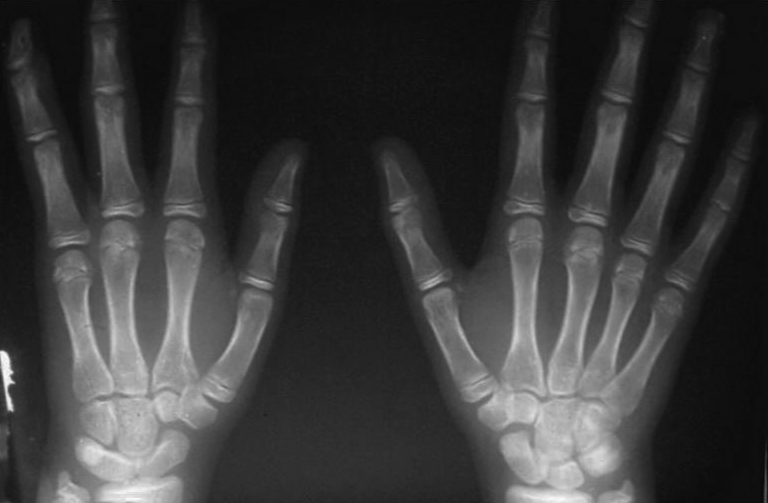

The first patient was a 12-year-old boy with type 1 deficiency (ulnar-deficient hand without radial or central hand anomalies). Radiographs of the affected right hand showed complete longitudinal absence of the small finger ray (phalanges and metacarpal), lunate-triquetral coalition, hypoplasia of the hamate, and incomplete duplication of the distal phalanx of the ring finger (Figure 1).

The second patient was a 9-year-old boy with a type 1 deficiency (ulnar-deficient hand with radial hand anomalies). Clinically, the affected left hand had 3 fingers (oligodactyly with thumb). There was hypoplasia of the thenar and aplasia of the hypothenar muscles. Despite the cosmetic problems, the patient had a functional hand and a stable wrist. Radiographs showed a complete longitudinal absence of the small and ring finger rays, pseudoepiphysis of the second metacarpal, capitate-hamate coalition, delayed skeletal age of the wrist and forearm bones, and narrowing of the first web (Figure 2). The distal ulnar epiphysis is cartilaginous. The deficiency could potentially be type 2A in the case of negative ulnar variance.